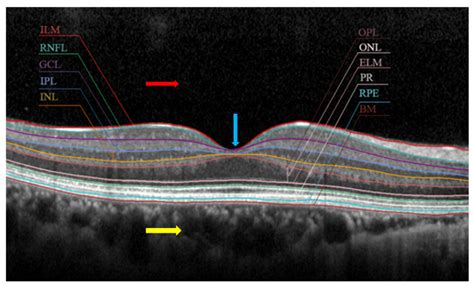

When discussing the complexities of human vision, the retina often takes center stage as the primary sensing organ. However, within the retina, two specific regions are critical for our ability to see fine detail, read, and recognize faces: the macula and the fovea. Understanding the Macula Vs Fovea distinction is essential for grasping how light is converted into the clear, sharp images we perceive every day. While these terms are frequently used interchangeably in casual conversation, they actually refer to distinct anatomical structures with different functions and cellular compositions.

The macula is a small, specialized area located at the center of the retina, directly behind the pupil. It is a yellowish, oval-shaped spot measuring about 5 to 6 millimeters in diameter. Despite its relatively small size compared to the entire retina, the macula is responsible for our central vision, which is the vision we use for tasks that require high visual acuity.

Think of the macula as the "high-resolution" zone of your eye. When you look directly at an object, the light from that object is focused onto the macula. It is packed with millions of photoreceptor cells—specifically, cones—that provide the detailed, colored vision necessary for reading, driving, and identifying small details.

If the macula is the high-resolution zone, the fovea is the "ultra-high-definition" center of that zone. The fovea is a tiny, pit-like depression located exactly at the very center of the macula. It is significantly smaller than the macula, measuring only about 1.5 millimeters in diameter.

The fovea is responsible for the absolute sharpest vision. While the macula provides detailed central vision, the fovea is what you use when you focus intently on a single point, such as looking at a specific word on this page or the thread of a needle. Without the fovea, our vision would be functional but perpetually blurry, lacking the ability to resolve fine details.

To better understand the relationship between these two, it is helpful to look at their structural and functional differences side-by-side. The macula acts as the container, while the fovea acts as the focal point within that container.